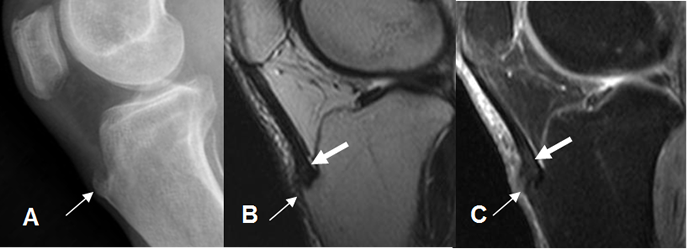

Fig 149 B. Tendinitis del patelar.

A: Rx lateral, B: RM sagital en T2 y C: RM sagital en STIR. Formación de osteofito sobre la inserción del tendón patelar (Flechas delgadas), el cual muestra alteración de su señal, por proceso inflamatorio. (Flechas gruesas).